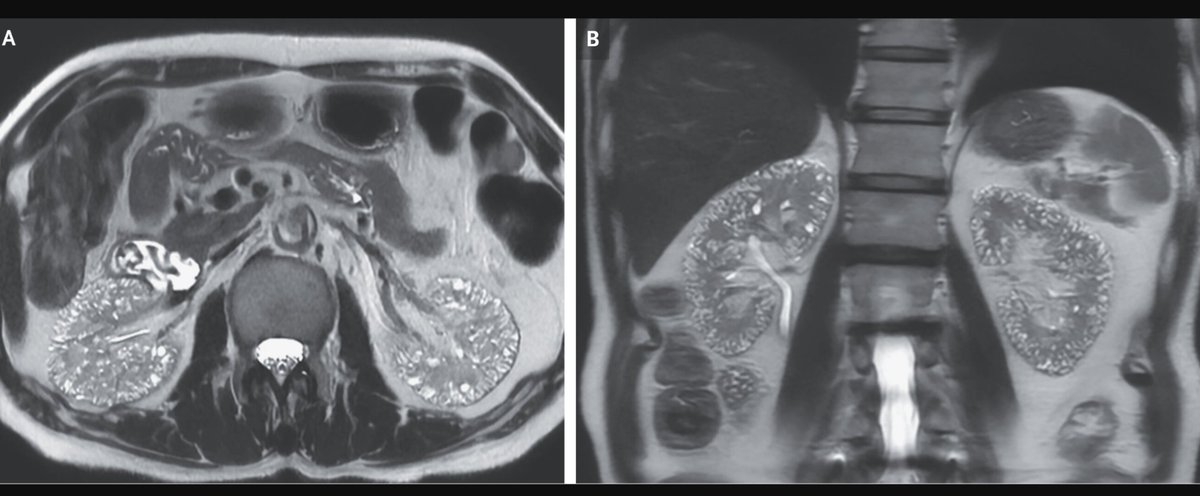

My respect and recognition for the nephrologists (or related) of #POCUS on #WorldKidneyDay. NephroPOCUS, Ahmed T Abdellah, Eduardo R Argaiz, Pierpaolo Di Nicolò, francesco corradi, Joaquín Martínez Yesterday we admitted this patient with nephrocalcinosis, staghorn calculi, hydronephrosis, and a UTI!

Imagen en nefrocalcinosis NephroPOCUS Dr. Oswaldo Ramos DrDopplerPoder Javier Teigell Medicina Interna. Lo miro y mañana te digo. Yale Tung-Chen Samuel García Rubio Curro Miralles José António Briote Mariz ABCDEcografía Pierpaolo Di Nicolò Jose Maria Palacin Jorge Zegarra Fco. Javier Alvarez Higueras Ignacio M Sánchez 🇪🇦🇪🇺🇺🇦🎸 M. Solimán Berchíd Debdi EcosemFYC USPed GT Ecografía SEMI